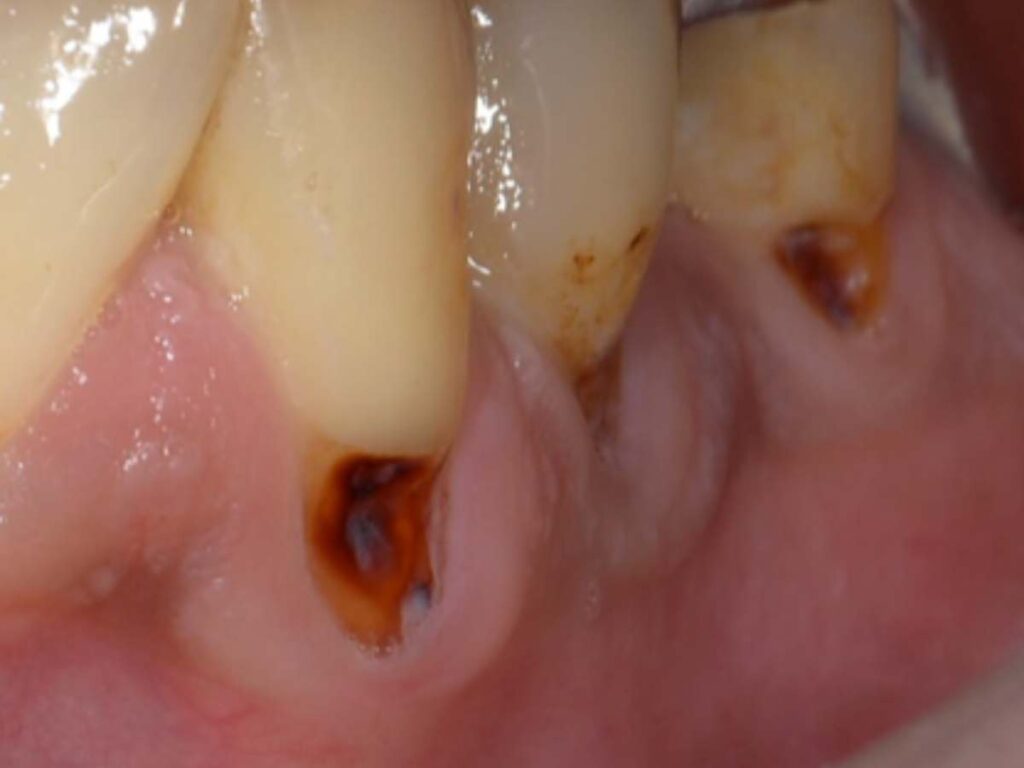

今回の症例は下顎犬歯〜小臼歯に生じた歯肉退縮部の根面う蝕でした。歯ぐきが下がったことで歯根が露出し、その部分に虫歯が発生してしまったケースです。そこで今回は単純に虫歯を詰める治療ではなく、歯周形成外科(歯肉移植術)を併用した治療を行いました。

✔ 根面う蝕(虫歯)を丁寧に除去

✔ 露出している歯根を歯肉移植で被覆

✔ 強く安定した角化歯肉を再建

- 術前側方面観

- 術前正面観